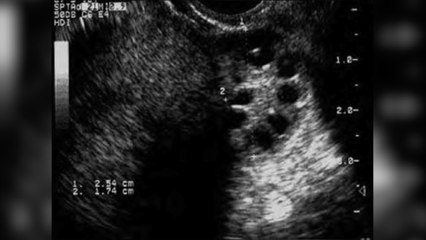

52% UAE residents aware of polycystic ovarian syndrome